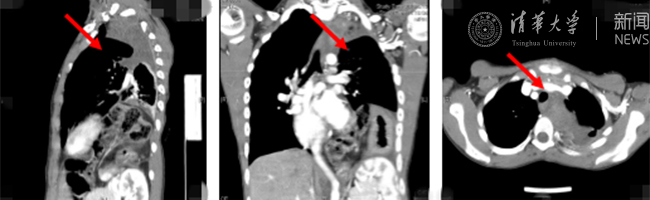

清华新闻网8月30日电(通讯员  杨峰)如图中所示,本是正常人心脏、左肺的位置,被发于神经鞘的巨大肿瘤占据,导致一位刚满12岁的男孩胸痛、咳嗽、呼吸困难。近日,北京清华长庚医院神经外科与胸外科联手,由神经外科王贵怀主任主刀,成功为男孩切除胸腔巨大神经鞘肿瘤。

患者胸腔内巨大的肿瘤。

半年前,患者经常会出现胸痛、咳嗽和呼吸困难,在当地医院检查发现左侧胸腔巨大占位,左肺及心脏明显受压。王贵怀大夫接诊,仔细查体了解病情,并反复认真阅片后,认为左侧胸腔巨大肿瘤来自于胸椎椎管内,神经鞘瘤可能性大。该肿瘤体积巨大,占据绝大部分胸腔空间,压迫左肺、纵隔大血管及膈肌。